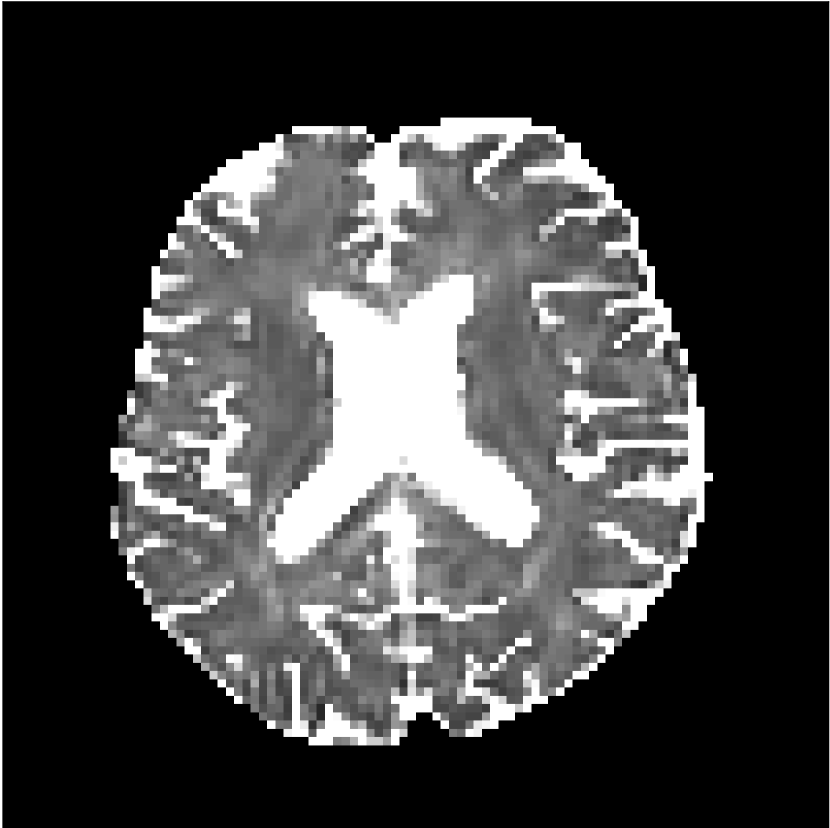

Figure 10 compares mean diffusivity maps across various partial Fourier factors between the CCNN and state-of-the-art methods.

No PF

7/8 PF

6/8 PF

5/8 PF

SoA

CCNN

Figure 10: Comparison of mean diffusivity (MD) parameter maps across PF factors of 5/8ths, 6/8ths, 7/8ths, and without PF (No PF). The methods include state-of-the-art (SoA) and CCNN methods. Without partial Fourier, both methods are similar; however, as the PF factor increases, substantial artifacts are introduced in the SoA method, particularly around the lateral ventricles. The CCNN method is able to reduce the introduction of artifacts.

The methods perform similarly without partial Fourier acceleration, but as partial Fourier acceleration increases, the image is continually degraded in the SoA method, with "black voxels" appearing around the lateral ventricles. The CCNN method mitigates the appearance of these artifacts in the parameter maps.